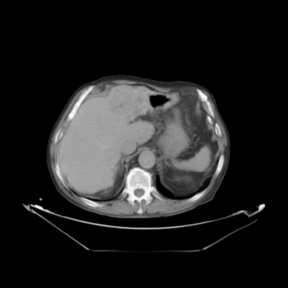

In addition to the previous measurements, the visual outcomes of two of the experiments are shown in [[#img-3|Figures 3]] and [[#img-4|4]], whose purpose is to highlight the most illustrative differences (from a medical point of view) between the results provided by the compared methods. In  [[#img-3|Figure 3]], we observe a normal size of the liver, with discretely irregular contours and homogeneous signal intensity. In hepatic segment II, there is a lesion of 40 mm of maximum axis, encapsulated and with well-defined contours and heterogeneous enhancement in arterial phase (after administration of intravenous contrast), suggestive of hepatocellular carcinoma (HCC). In this slice of the CT scan, we can also observe the aorta that shines in the arterial phase, the lower area of the stomach and the upper area of the spleen. In  [[#img-4|Figure 4]], the liver has a normal size with discretely irregular contours in relation to changes due to chronic liver disease. In hepatic segment IV, a 36 mm diameter focal lesion is identified, which has arterial phase enhancement with a small area of necrosis of 13 mm; it corresponds to a HCC previously chemoembolized with partial necrosis. In this slice of CT, we can also observe the aorta, the gastric chamber and the spleen. When comparing the two methods under study, it can be seen how in  [[#img-3|Figure 3]] the resulting registered datasets are very similar. However, looking closely, it can be noticed that in the right part of the image (left side of the patient) the shape and width of the structures corresponding to the stomach and the spleen in  [[#img-3|Figure 3]](d) match better those in the reference dataset. Likewise, the part of the rib at the upper right of the image is more similar to the same region in the reference dataset by using the proposed method. Regarding the experiment shown in  [[#img-4|Figure 4]], it can be easily appreciated how the geometrical matching (with respect to the reference dataset,  [[#img-4|Figure 4]](a)) of the structures in the right side of the image (specially the gastric chamber) is visually more satisfactory in  [[#img-4|Figure 4]](d). Moreover, the area of tumor necrosis which results from the proposed method is also slightly better aligned.

In addition to the previous measurements, the visual outcomes of two of the experiments are shown in figures Fig.[[#img-3|3]] and Fig.[[#img-4|4]], whose purpose is to highlight the most illustrative differences (from a medical point of view) between the results provided by the compared methods. In Fig.[[#img-3|3]], we observe a normal size of the liver, with discretely irregular contours and homogeneous signal intensity. In hepatic segment II, there is a lesion of 40 mm of maximum axis, encapsulated and with well-defined contours and heterogeneous enhancement in arterial phase (after administration of intravenous contrast), suggestive of hepatocellular carcinoma (HCC). In this slice of the CT scan, we can also observe the aorta that shines in the arterial phase, the lower area of the stomach and the upper area of the spleen. In Fig.[[#img-4|4]], the liver has a normal size with discretely irregular contours in relation to changes due to chronic liver disease. In hepatic segment IV, a 36 mm diameter focal lesion is identified, which has arterial phase enhancement with a small area of necrosis of 13 mm; it corresponds to a HCC previously chemoembolized with partial necrosis. In this slice of CT, we can also observe the aorta, the gastric chamber and the spleen. When comparing the two methods under study, it can be seen how in Fig.[[#img-3|3]] the resulting registered datasets are very similar. However, looking closely, it can be noticed that in the right part of the image (left side of the patient) the shape and width of the structures corresponding to the stomach and the spleen in Fig.[[#img-3|3]](d) match better those in the reference dataset. Likewise, the part of the rib at the upper right of the image is more similar to the same region in the reference dataset by using the proposed method. Regarding the experiment shown in Fig.[[#img-4|4]], it can be easily appreciated how the geometrical matching (with respect to the reference dataset, Fig.[[#img-4|4]](a)) of the structures in the right side of the image (specially the gastric chamber) is visually more satisfactory in Fig.[[#img-4|4]](d). Moreover, the area of tumor necrosis which results from the proposed method is also slightly better aligned.